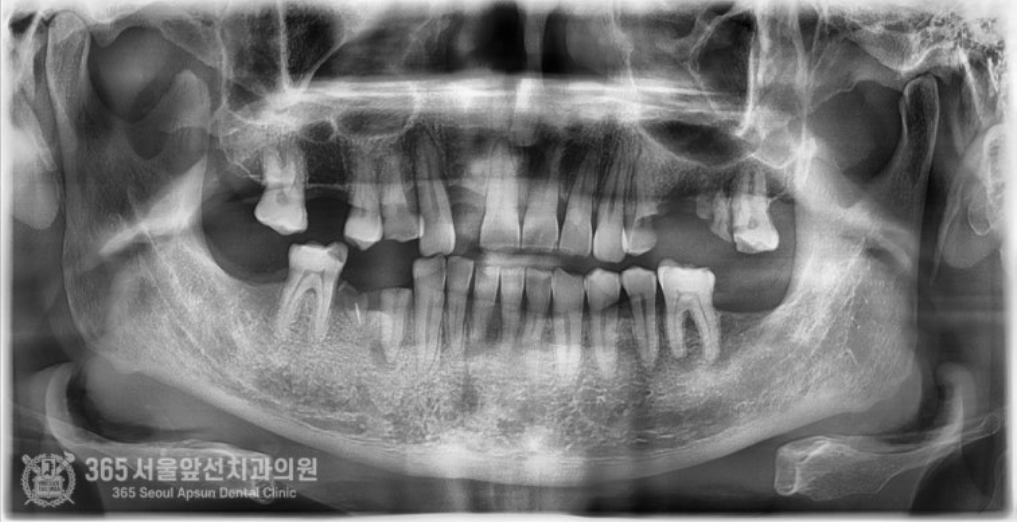

안녕하세요. 석바위시장치과 365서울앞선치과의원입니다. 오늘은 전체 임플란트 치료증례를 살펴보겠습니다. 예전에 치료해드렸던 환자분께서 소개해주신 환자분이십니다. 빵도 사다주시고 참 감사했던분이신데요 ㅎㅎ 촬영일시 : 2024.08.03. 처음 내원당시 상태는 이가 많이 없어서 제대로 밥을 먹을 수가 없어요. 잘 웃지도 못하구요. 이가 많이 없으셔서 식사도 불편하고 특히 사회생활에 불편감이 있으시다고 하셨습니다. 진단과정을 거쳐 발치할 치아는 발치하고 살려서 쓸 수 있는 치아는 살려쓰는 것으로 계획하여 치료를 진행하였구요. 촬영일시 : 2024.10.11. 임플란트가 모두 식립된 상태입니다. 치아가 없는 자리와 치아를 발치한 자리에는 임플란트를 식립하여 튼튼하게 보철물을 제작해드렸구요. 살려서 쓸 수 있는 치아는 신경치료 후 크라운으로 보강하여 마무리해드렸습니다 ㅎㅎ 치료기간은 대략 3~4개월 정도 걸렸습니다. 촬영일시 : 2025.01.12. 치료 종결 후 엑스레이 사진입니다. 임플란트가 반듯하게 잘 식립되었네요. 치아도 기존 치아색상과 조화를 이룰수있게 자연스러운 색조로 제작해드렸습니다ㅎㅎ 아주 만족하셨어요. 임플란트 치료하고 나서 인상이 확 바뀌었다는 얘기를 많이 들었어요. 이런 말씀을 해주실때마다 의사로서 뿌듯함을 느낍니다 ^^ 오늘은 소문을 듣고 내원하신 환자분을 전체 임플란트 치료를 통해 만족시켜드린 증례를 소개해봤습니다. 앞으로도 좋은 증례로 찾아뵙겠습니다. 석바위시장치과 365서울앞선치과의원이었습니다. 감사합니다. [ 치료기간: 2024년 8월3일 ~ 2025년 1월 12일 ] ※ 365서울앞선치과의원의 모든 포스팅은 각 진료과 의료진이 직접 작성합니다. 365서울앞선치과의원 블로그의 임상 케이스 게시물은 환자분께 의학적으로 정확하고 상세한 정보를 드리기 위해 각 진료과 의료진이 직접 작성하며, 모든 증례 사진은 본원 의료진이 직접 시술한 증례를 촬영한 것으로, 의료법 제23조, 제56조에 의거하며 환자분의 동의를 얻어 포스팅에 사용하였습니다. 또한 해당 케이스는 본 환자분의 치료 결과이며, 환자 상태에 따라 치료의 결과는 달라질 수 있습니다. |